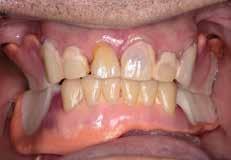

Prothetische Rehabilitation nach Resektion

Der Patient wurde im Zuge der Tumornachsorge wieder an der Universitätszahnklinik Wien vorstellig. Am Beginn der prothetischen Fallplanung wurden montierte Situationsmodelle erstellt und ein aktueller Röntgenstatus erhoben. Intraoral bestätigte sich, dass der resezierte Bereich mittels eines Zungentransplantates gedeckt wurde.

Da der Patient bereits bestehende alte

Modellgussprothesen für den Oberkiefer und den Unterkiefer hatte, wurden diese herangezogen und als Immediatersatz erweitert sowie unterfüttert. Während der Planung entschied sich das behandelnde Ärzt:innen-Team sowohl im Ober- als auch Unterkiefer für eine teleskopierende Metallgerüstprothese. Zahn 11 wurde mittels Adhäsivtechnik aufgebaut und darüber hinaus für Zahn 21 eine Einzelzahnzirkonkrone geplant. Um eine adäquate Retention der Kronen gewährleisten zu können, wurden an fünf Zähnen gegossene Stiftaufbauten eingegliedert (Abb. 6 u. 7).

Wachsaufstellung (Abb. 8–10) erhielt das zahntechnische Labor die Freigabe zur Erstellung der Primärund Sekundärteleskope mit Gerüsten. Diese wurden insbesondere auf ihre Passgenauigkeit und Schaukelfreiheit im Kiefer überprüft. Des Weiteren wurde bei der Erstellung auf eine Unterspülbarkeit des transplantierten Gebietes geachtet. Nach erfolgter Wachsaufstellung auf Gerüst wurde die Fertigstellung der Teleskopprothesen und der Einzelzahnzirkonkrone in

Auftrag gegeben. Für Zahn 11 wurde vom zahntechnischen Labor ein entsprechendes Mock-up mit Schiene zur Übertragung erstellt (Abb. 11–23). Anschließend an die komplikationslose Eingliederung der Arbeit erfolgte eine Kontrolle sieben Tage nach erfolgter Übergabe (Abb. 24, Seite 7). Nach der Durchführung von minimalen Korrekturen an der Okklusion wurde der Patient in den Recall entlassen.•